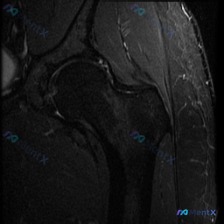

这张髋关节MRI冠状位T2加权像,最可能提示什么病变?

最近看到一张髋关节MRI冠状位T2加权像的病例资料,患者主要关注是否存在髋臼唇病变。先看一下图像的基本表现:股骨头形态完整,皮质光整,内部信号正常;关节间隙尚可,未见明显异常狭窄或增宽;髋臼外上方盂唇结构连续,未见明显撕裂导致的异常高信号裂隙或撕脱样改变;外侧大转子周围软组织可见局部高信号影(水肿)。

大家第一眼看到这张图像,最可能考虑什么诊断?